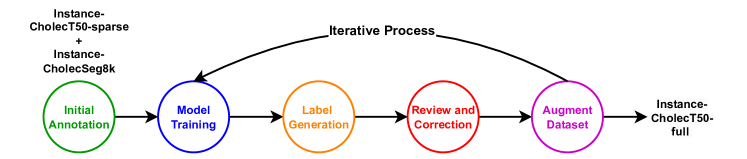

For the CholecT50-full dataset, which requires annotations for full sequences (nearly 30,000 frames from 15 sequences extracted at 1 fps), we opted for a semi-automatic approach with a human-in-the-loop, utilizing a deep learning model to assist in producing instance segmentation annotations.

-

1.

Initial Annotation: We began with initial annotations from the Instance-CholecSeg8k dataset. Since CholecSeg8k only contains two tool categories (Grasper and Hook), which is fewer than the seven tool categories identified for annotation, we performed additional annotations using the annotation tool. We focused on images that included the new instruments. The combined dataset of Instance-CholecSeg8k and these initial annotations provided a foundation to start the semi-automatic pipeline for generating labels.

-

2.

Model Training: A deep neural network, the Real-Time Models for Object Detection and Instance Segmentation Large (RTMDet-Ins-l) [19], was trained using the available annotated datasets (Instance-CholecSeg8k and Instance-CholecT50-sparse).

-

3.

Annotation Proposal Generation: Leveraging the trained model, we generated annotations for a larger portion of the unannotated data.

-

4.

Annotation review and correction: Human annotators reviewed the model-generated annotations and corrected any errors or inaccuracies, ensuring the quality and accuracy of the annotations.

-

5.

Augment training dataset: The machine learning model was retrained using the expanded training dataset, incorporating the corrected annotations. This iterative process enhanced the model’s performance. The model was trained twice: initially, with an annotation set of approximately 11k images and their corresponding labels. The trained models was used to generate labels for about 10k images. Human annotators corrected labels for 5k of these images. The model was then retrained with 21k images, generating labels for another 17k images, with labels for 4k images requiring human annotators for correction.

A visual representation of our semi-automatic approach to annotation can be seen in Figure 6.